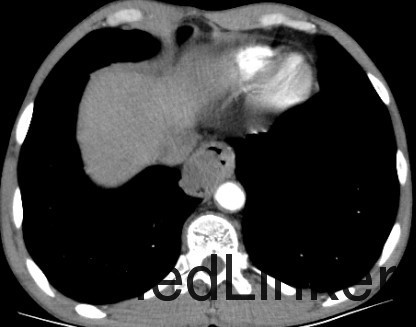

主诉:胸骨后隐痛40天,伴嗳气10天。 现病史:患者40天前无明显诱因出现胸骨后隐痛,呈间断性,无明显加重缓解因素,无放射痛。无进食哽噎感,无吞咽困难,无发热咳嗽,无胸闷心悸,无腹痛腹胀,无头晕头痛。10天前开始,患者出现嗳气不适,胸骨后疼痛无明显加重。于奈曼旗人民医院就诊,查纤维胃镜示“食管占位”。今为求进一步治疗,来我院就诊,门诊以“食管占位”为诊断收入院。患者病来一般状态好,小便正常,大便次数少,腹泻、便秘交替,饮食睡眠好,近期体重减轻约8KG。 。 既往史:否认高血压、冠心病、糖尿病等疾病史;否认肝炎结核等传染病病史;4年前颌面部外伤,否认手术史,否认输血史。否认食物及药物过敏史。预防接种史不详。

查体:T:36.4℃,P:78次/分,Bp:131/77mmHg,R:16次/分。神清语明,步入病房,查体合作,营养状态略差,皮肤粘膜无黄染,结膜无苍白,浅表淋巴结未触及肿大,气管居中,胸廓对称无畸形,呼吸运动正常,双肺叩诊清音,未及明显罗音。心音钝,律齐。腹平软,无压痛及反跳痛,肝脾肋下未触及。肝区叩痛(-),双下肢无水肿,脊柱四肢活动无异常。 辅查:胃镜(奈曼旗人民医院,2015-10-28):食管占位。

诊断 : 食管占位 治疗:入院后完善相关检查,胃镜病理未能予以确定诊断为恶性肿瘤。患者家属拒绝再次胃镜病理检查,要求行手术治疗。 后为解除梗阻症状,提升患者生活质量,按食管恶性肿瘤准备行手术治疗,术中切除肿物并剖开,内部质韧,肿物表面局部溃疡性改变,冰冻回报:平滑肌瘤伴鳞状细胞癌,患者现术后康复中,病理尚未回报。